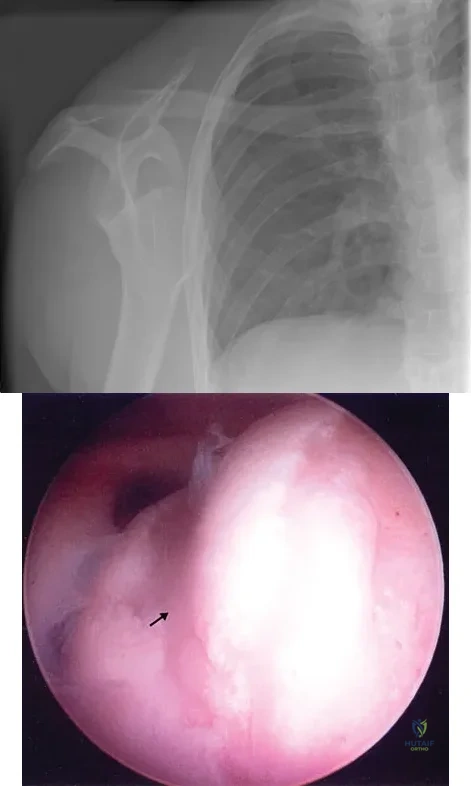

Question 90

Figure 4a shows the radiograph of a 20-year-old man who has an injury to the right shoulder. Figure 4b shows an arthroscopic view (posterior portal). The arrow points to a

Explanation